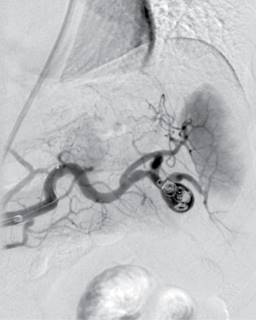

Femenino de 41 años, con antecedente de hipotiroidismo diagnosticado a los 21 años, actualmente sin tratamiento médico desde los 40 años por aparente control, diagnóstico de miomatosis uterina a los 40 años, sin tratamiento; antecedente de dos cesáreas, última a los 23 años, sin complicaciones. Accidente automovilístico con volcadura a los 40 años, sin daño orgánico aparente. Inicia padecimiento actual posterior a accidente automovilístico ocurrido un año previo con dolor en hipocondrio izquierdo, de tipo intermitente, punzante, sin irradiaciones, sin agravantes ni atenuantes; a la exploración física presenta dolor en hipocondrio izquierdo a la palpación profunda, resto sin datos patológicos. Se realizó ultrasonido con hallazgos compatibles con aneurisma de la arteria esplénica y colelitiasis, se complementa abordaje diagnóstico con angiotomografía de aorta abdominal encontrando arteria esplénica de calibre normal, con dilatación focal sacular en segmento distal compatible con aneurisma de 17.7 × 15.9 mm y cuello de 5.5 mm, con trombo mural de 2 mm, sin signos de ruptura, litiasis vesicular y miomatosis uterina. En manejo conjunto con angiología se realiza embolización selectiva con colocación de coils, sin complicaciones aparentes (Figura 1). En el seguimiento inmediato, la paciente presenta dolor abdominal y leucocitosis, se realiza nueva angiotomografía con datos sugestivos de oclusión de arteria esplénica e infarto esplénico (Figura 2). Por los hallazgos comentados se decide realizar esplenectomía y colecistectomía convencional mediante abordaje quirúrgico con incisión en línea media, supraumbilical, con los siguientes hallazgos: vesícula biliar de paredes delgadas, múltiples litos en su interior de 5-10 mm aproximadamente, arteria cística de 2 mm, conducto cístico de 3 mm, bazo de 13 × 10 cm aproximadamente, con múltiples zonas isquémicas, aneurisma de la arteria esplénica a nivel de hilio esplénico, posterior a su bifurcación (Figura 3). Cursa el postoperatorio sin complicaciones, por lo que fue egresada tres días después de la cirugía, recibió vacunación correspondiente para pacientes esplenectomizados. Reporte histopatológico con hallazgos de aneurisma de arteria esplénica con ateroesclerosis, parénquima esplénico con vasos congestivos y colecistitis crónica litiásica.

Figura 2: Angiotomografía abdominal. A) En corte coronal se identifica material de densidad metálica correspondiente a coils localizados en segmento distal de arteria esplénica previos a hilio esplénico. B) Se observa opacificación y captación del contraste a nivel esplénico de forma irregular heterogénea tanto en la fase arterial como venosa, apreciando una zona extensa que involucra a la mayor parte del parénquima esplénico desde el hilio, sólo respetando el polo superior y el inferior compatible con infarto.